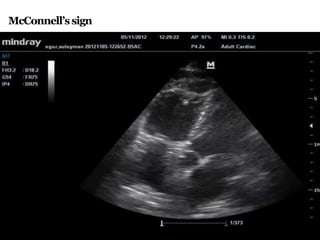

ECHOCARDIOGRAPHY

• Presenceof unexplainedright ventricular volume or pressure

overloadshouldsuggestthe possibility of embolism andleadto

confirmatory testing.

• TEEhasbetter sensitivity and specificity especiallyin casesof

proximal embolus,reachingupto 90%.comparedto 50%in TTE.

• It helps to detect RV enlargement & RWMA a/wPTE

(McConnell’s sign - hypokinesia of RV free wall with normal

motion of RV apex is best known indirect sign of PE)

McConnell’ssign

ECHOCARDIOGRAPHY • Presenceof unexplainedrightventricular volume or pressure overloadshouldsuggestthe possibility of embolism andleadto confirmatory testing. • TEEhasbetter sensitivity and specificity especiallyin casesof proximal embolus,reachingupto 90%.comparedto 50%in TTE. • It helps to detect RV enlargement & RWMA a/wPTE (McConnell’s sign - hypokinesia of RV free wall with normal motion of RV apex is best known indirect sign of PE)